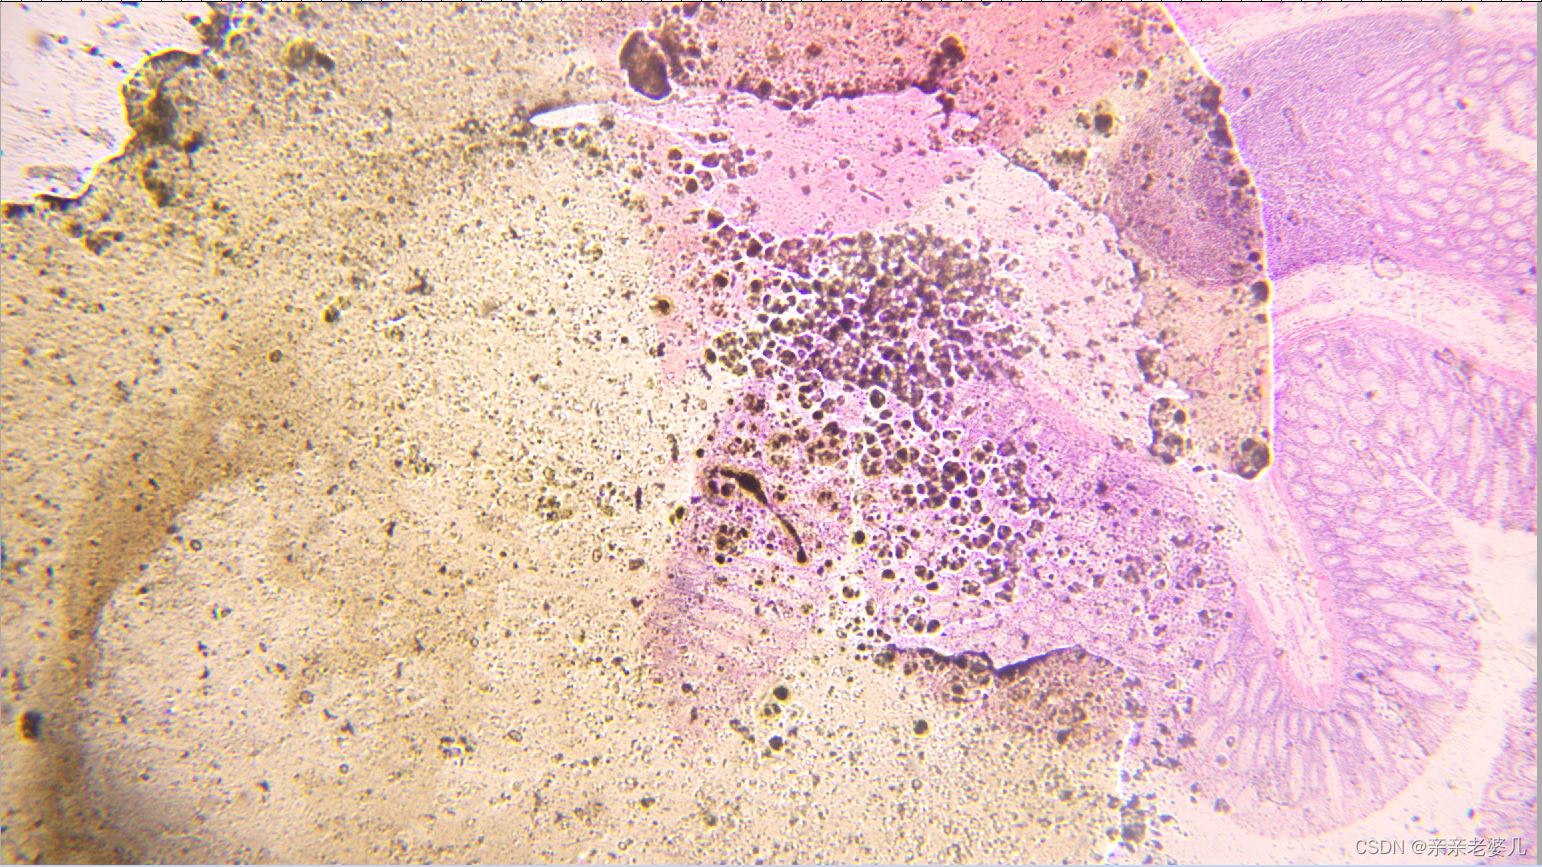

9. 千奇百怪的疾病——疾病的显微诊断及大体实物标本展示

如何获得标本:

手术 取材 包埋 蜡块 切片 染色

宫颈鳞癌

正常小肠